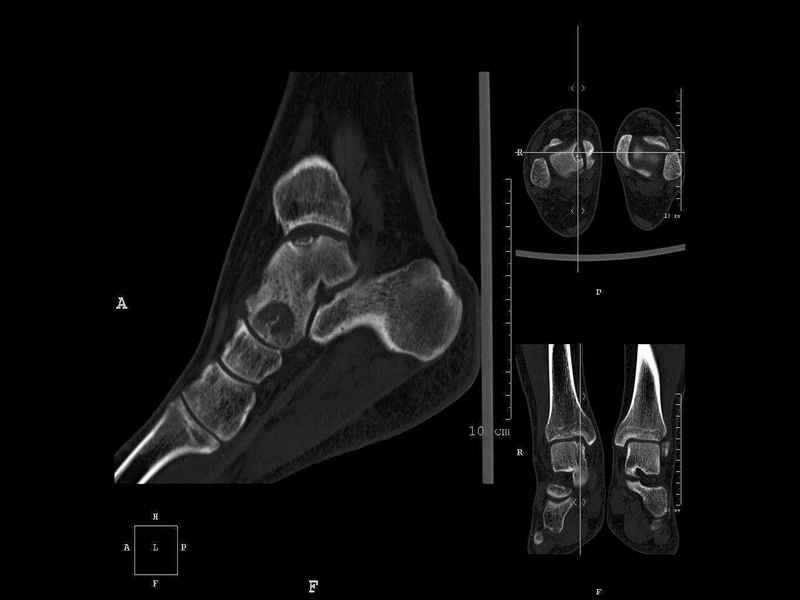

Рассекающий остеходрит + киста шейки тарана

Уважаемые коллеги, обратился за помощью пациент, мужчина, 25 лет. С жалобами на болевой синдром в области голеностопного сустава и среднем отделе стопы.

Травму отрицает. Со слов, болевой синдром в течении 1 года. Последние 1-1.5 мес периодически вынужден пользоваться костылями. После ограничения нагрузки боли уменьшаются. Соматически здоров. До появления болей активно занимался рукопашным боем.

На СКТ картина рассекающего остеохондрита блока таранной кости, киста шейки таранной кости с признаками импрессии суставной поверхности. А также - разрастания переднего края б\берцовой кости сопровождающиеся клиникой импиджмент синдрома.

Предполагаемый план лечения- удаление свободного фрагмента суставного хряща из трансмаллеолярного доступа с рассверливанием поверхности дефекта, кюретаж кисты шейки с заполнением полости биокомпозитом + дебридмент переднего отдела голеностопного сустава.

Прошу высказать своё мнение, за и против, предполагаемого плана лечения.

1. Есть ли необходимость в улучшении васкуляризации таранной кости (например подтаранный артродез).

2. Учитывая планируемое применение биокомпозитного цемента целесообразно ли заполнение им дефекта блока таранной кости с моделированием края суставной поверхности.